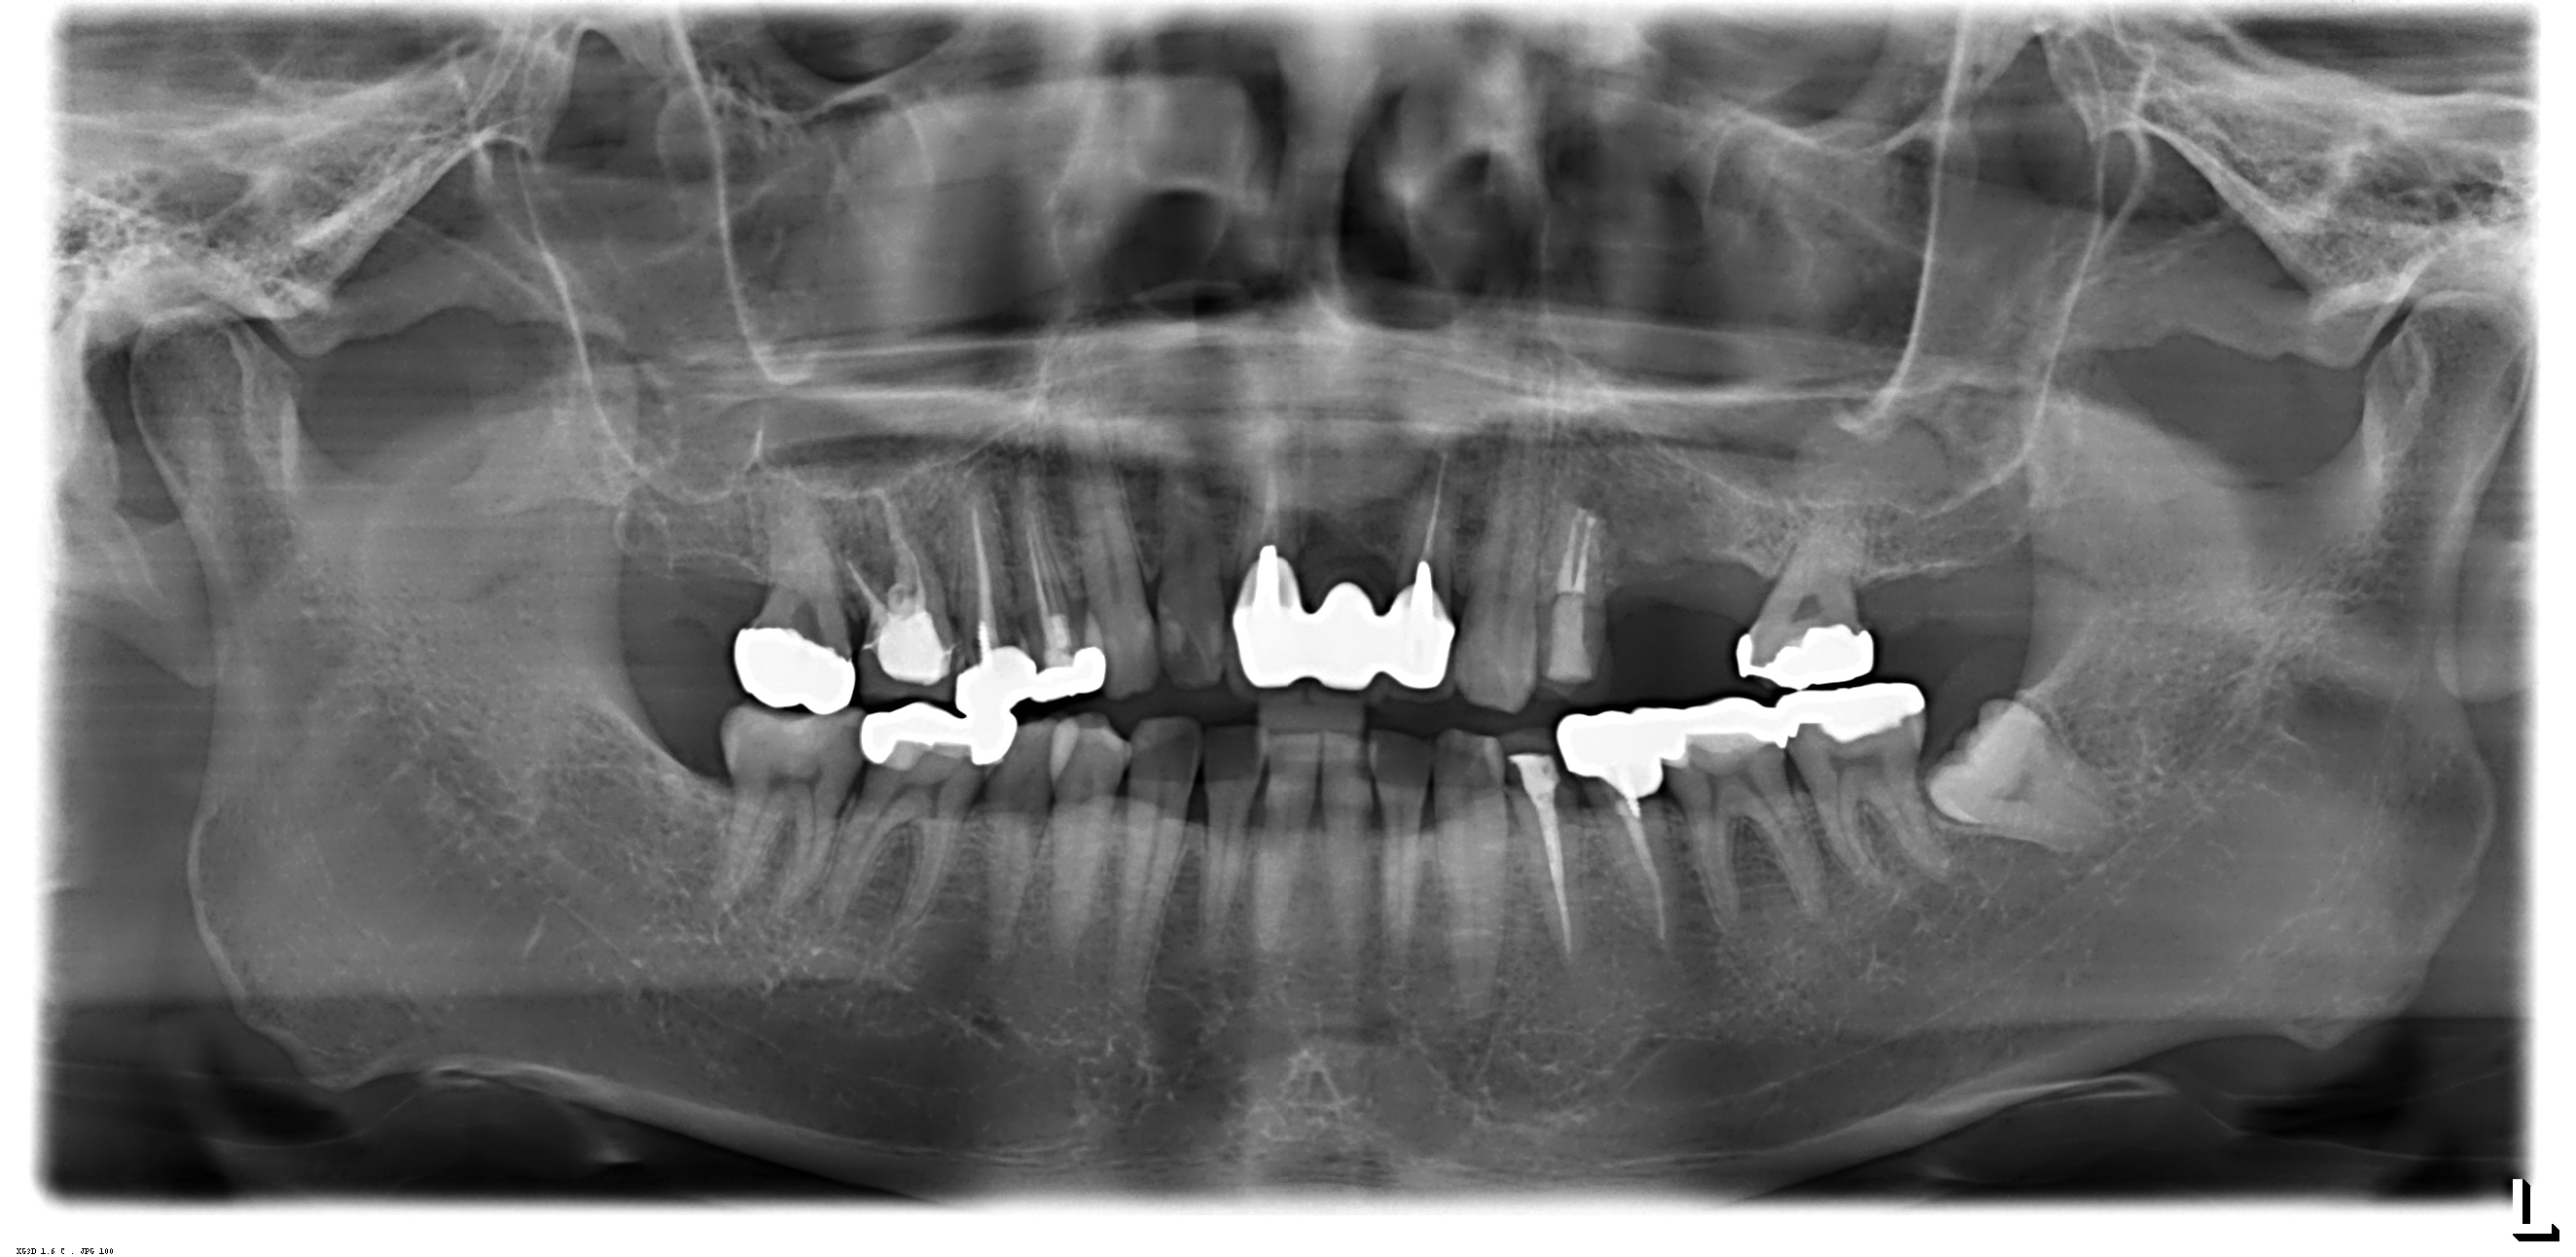

対象は左上上顎部の5番と6番の2本で、下記状況のもと、医師から治療提案を受けておりますが、海外での外国人医師による治療に不安を感じており、日本の歯科医の先生にご意見を頂ければと思います。

・5番目は骨が十分あるが、6番は6.7mmほどしか骨がありません

・5番は抜歯後1年弱、6番は3年半ほど経っています

また、医院にはCTがありますが、白黒のかなりぼやけた画像のCTで、そこにも少し不安を感じております。

> また、医院にはCTがありますが、白黒のかなりぼやけた画像のCTで、そこにも少し不安を感じております。